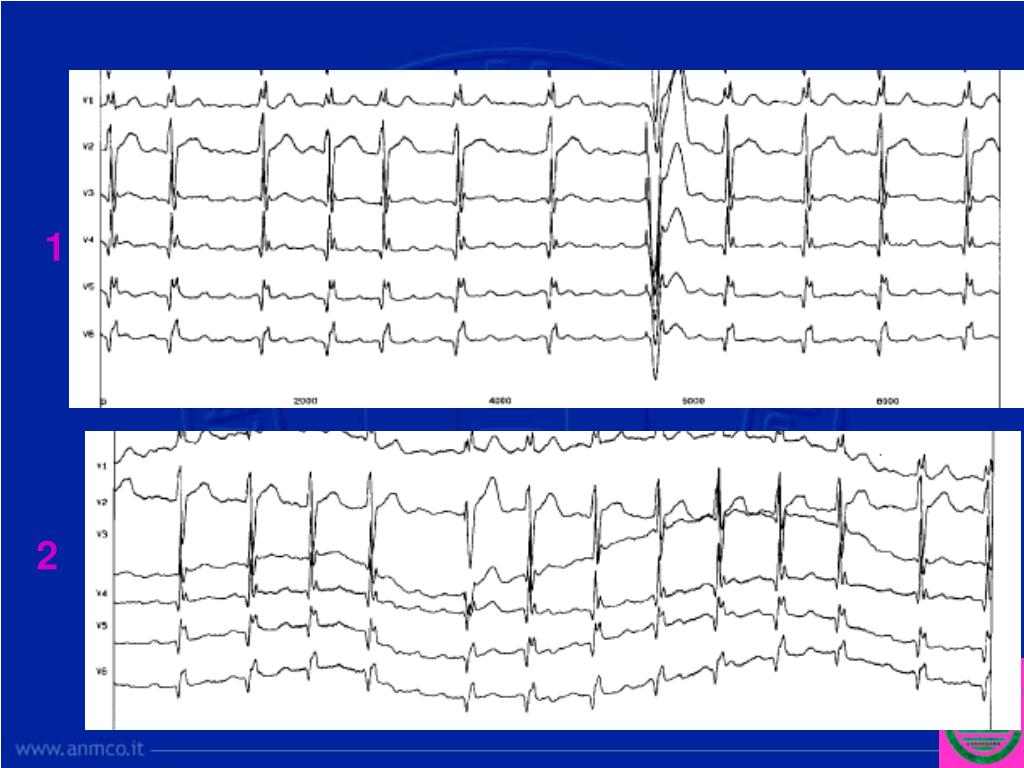

10. Subito dopo, durante la procedura, si osserva : Ciclo F-F 250 msec Onda F positiva in D1,D2,difasica in aVL, Isoelettrica in aVF, negativa in V1.

11. Il confronto ci fa apprezzare meglio le differenze:

20. Il passaggio da una deflessione negativa nelle derivazioni inferiori a deflessioni positive indica che il cambio di polarità all’ecg è associato con una alterata attivazione settale che cambia da caudocraniale a craniocaudale e riflette probabilmente una simile modificazione nella attivazione dell’atrio sinistro.

26. 1 2

27. 1 2